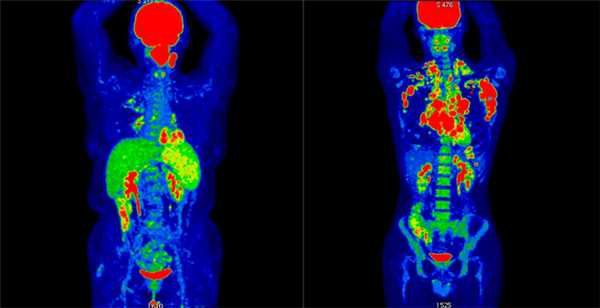

Результаты ПЭТ/КТ-исследования. Слева: неходжкинская лимфома (поражение левой небной миндалины и селезенки, поражение лимфоузлов выше диафрагмы. Справа: ходжкинская лимфома (поражение лимфоузлов по обе стороны от диафрагмы, с тенденцией к слиянию в массивные конгломераты, наиболее крупные в подмышечной области слева и в лимфоузлах средостения справа. III стадия)

На первой-второй стадии заболевания наблюдается ограниченное поражение лимфоузлов или одного экстралимфатического органа по одну сторону диафрагмы – мышечной перегородки между брюшной и грудной полостями. Как правило, самым первым симптомом лимфомы является увеличение лимфатических узлов. Биопсия пораженного лимфоузла и анализ на гистологию позволяют установить правильный диагноз.

На третьей-четвертой стадии выявляется поражение лимфоузлов по обе стороны от диафрагмы и/или нескольких экстралимфатических органов. Пациент жалуется на симптомы, характерные для большинства онкологических болезней: апатию, усталость, похудение, а также на симптомы, связанные с поражением конкретного органа.